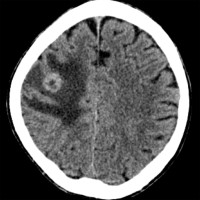

Intracerebral Hemorrhage of Left Thalamus

This was secondary to hypertension. Note the intraventricular spread.